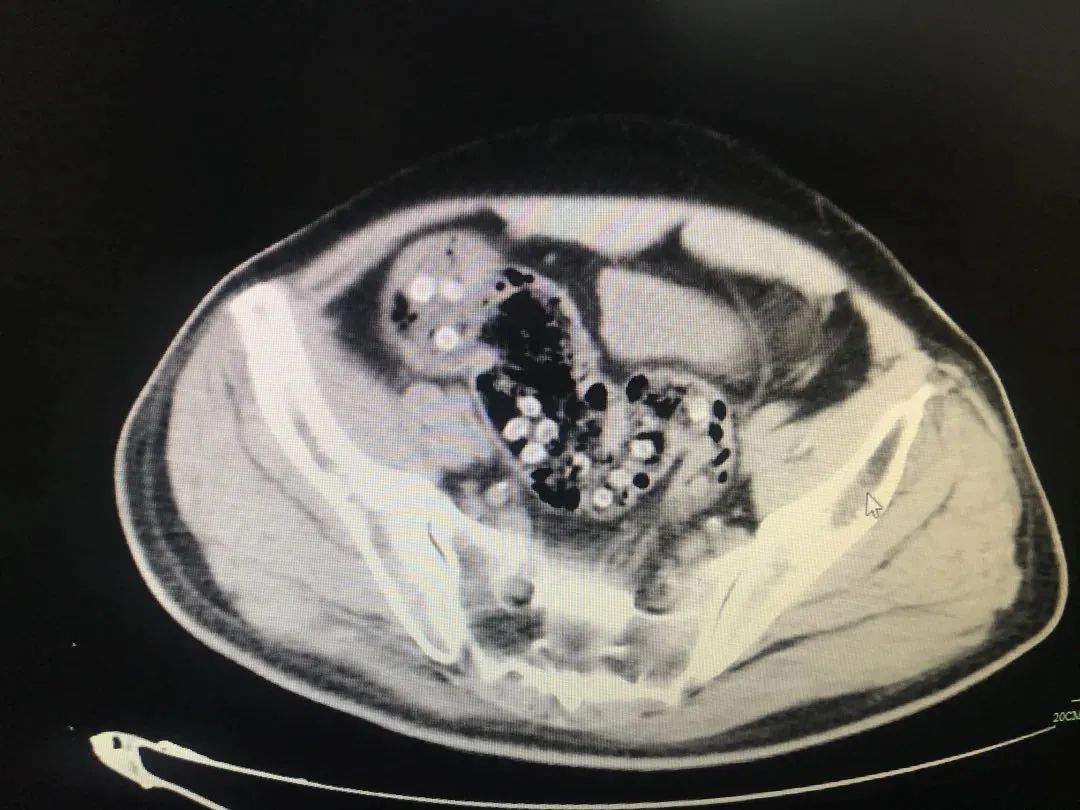

随后几天金大伯开始 感觉肚子有些胀痛,排便也不正常,还老是恶心呕吐 ,就去医院检查。太吓人了, 肠道里堵塞着密密麻麻的杨梅核 。

图片及新闻素材来自@广州日报